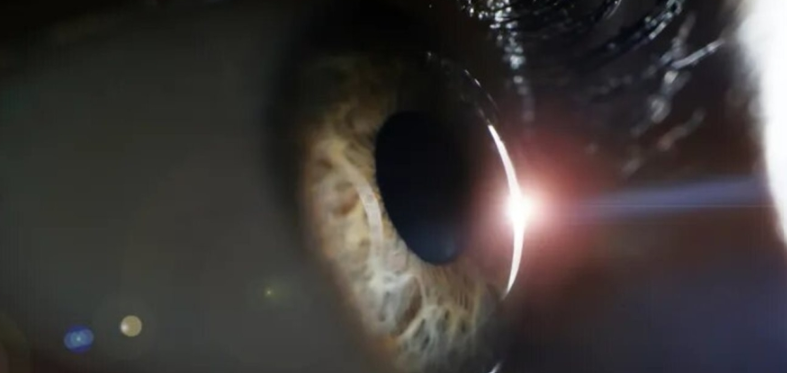

نجح فريق من العلماء في فك شفرة الآلام العضلية الغامضة التي تصيب بعض المرضى الذين يتناولون أدوية "الستاتين" الخافضة للكوليسترول، وهو الاكتشاف الذي قد يغير حياة الملايين حول العالم.

أظهرت الدراسة المنشورة في إحدى المجلات العلمية المرموقة أن بعض الأشخاص يمتلكون طفرة جينية تؤثر على عمل بروتين معين يُعرف بـ (P-gp)، وهو المسؤول عن ضخ الدواء خارج خلايا العضلات.

وعندما لا يعمل هذا البروتين بكفاءة، يتراكم الدواء داخل الأنسجة العضلية، مما يسبب الالتهابات والآلام المبرحة التي كانت تُصنف سابقاً على أنها "آثار جانبية غير مبررة".

تكمن أهمية هذا البحث في أنه يمهد الطريق لـ "الطب الشخصي"؛ حيث يمكن للأطباء الآن إجراء اختبارات جينية بسيطة قبل وصف الدواء، لتحديد الجرعة المناسبة أو اختيار بدائل لا تعتمد على هذا البروتين، مما يضمن استمرار حماية القلب من الكوليسترول دون التسبب في عجز حركي أو آلام عضلية للمرضى.